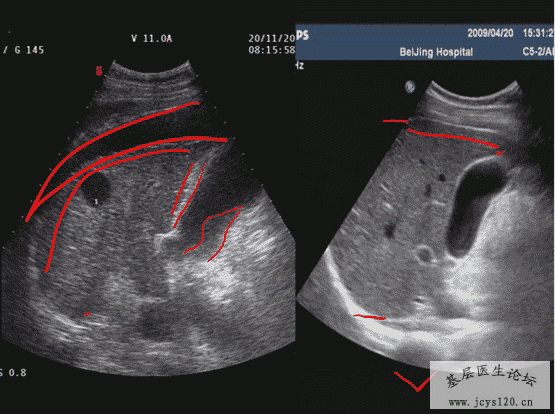

医学教育网讲义里面的精彩图片!